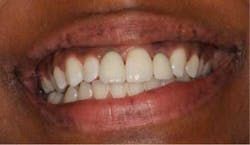

Fig. 6: Postoperative six weeks later.The patient returned for a follow-up eight months later (Fig. 7) and claimed she was careful not to bite into anything with her front teeth and wanted to know if they could be restored with permanent crowns. Impressions were taken and sent to the lab for fabrication of implant crowns. One year post-insertion, the final crowns and radiographs were taken (Figs. 8 and 8a).

Fig. 8: One year post-insertion — final crowns.